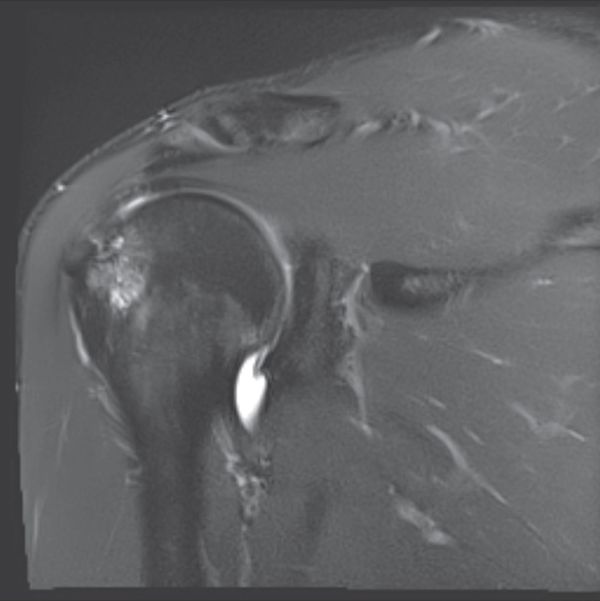

Computed tomography (CT) and magnetic resonance arthrography (MRA)

Examinations using intra-articular injection of a contrast medium (CT and MRA) are more reliable than simple MRI to visualize labral lesions and articular rotator cuff lesions (Figures).

MRA finding

Magnetic resonance arthrography (MRA) finding

Magnetic resonance arthrography (MRA) is standard, because it can also reveal the possible presence of a paraglenoid cyst (Figure) communicating with a labral tear, while allowing analysis of any concomitant tears (rotator cuff, osteochondral), and eliminate other causes of pain (acromioclavicular arthropathy, subacromial bursitis, tears relating to a painful and unstable shoulder).

Reliability depends on both machine and operator efficacy, but Jung et al. report a sensitivity of 85% and a specificity of 86% for superior labral tears.[41]

ABER position further improve sensitivity.[42]